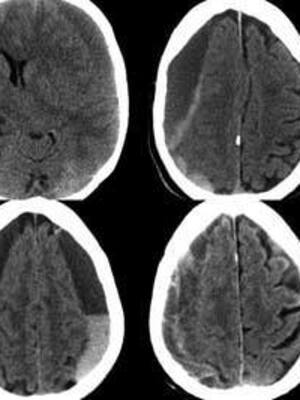

La sabiduría de la naturaleza diseñó para su cuidado unos anillos de seguridad y de protección. Un rompecabezas de huesos acoplados que forman el cráneo, es el casco preventivo que lo encierra y mantiene a salvo de golpes. De manera natural diseñó unas cubiertas para su protección y envoltura. Un par de finísimas sabanas trasparentes que se adosan a su superficie y son las que tienen el contacto íntimo y contienen como refrescante nutritivo el líquido cefalorraquídeo. Además, con función amortiguadora e inmunológica. La piamadre y aracnoides son estas finas envolturas. Entre estas sabanas y la tabla interna, irregular y rugosa del cráneo, le dio una envoltura más firme y protectora. Como una cobija encontramos la duramadre, la cubierta externa de la superficie del cerebro. Un hematoma subdural es el acumulo de sangre entre las sabanas intimas de la superficie y la duramadre. Hay que imaginarla como una mancha de aceite que arropa todo el encéfalo.

Unas finísimas velas entre el cerebro y la duramadre son unas venas colgando: las lábiles venas puentes. Golpes muy leves, pequeños, los cuales pueden pasar desapercibidos, las pueden romper. Así empieza el escurrimiento de sangre y en la medida que se va derramando se extiende la dispersión de la mancha sobre el cerebro. Llega un momento en que no se puede extender más en el plano horizontal, dos a tres semanas desde el golpe, y empieza a comprimir el cerebro. En este momento -ya enquistada- se inician los síntomas: dolor de cabeza, sensación de inestabilidad y perdida o lentitud de las funciones cognitivas del individuo. Los familiares lo notan confuso, desorientado y torpe en la marcha. “Viejito apendajao es hematoma asegurao” es la mnemotecnia que permite recordar toda la vida al estudiante de medicina su diagnóstico clínico.